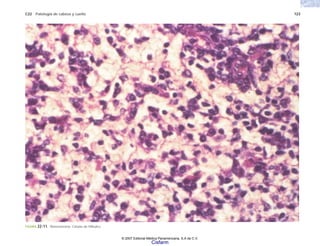

FIGURA 2-6. Linfoma difuso no Hodking con células en anillo de sello. Se observan cristales en el citoplasma de las células neoplásicas, que por inmunohistoquímica se demostró eran

de cadenas kappa.